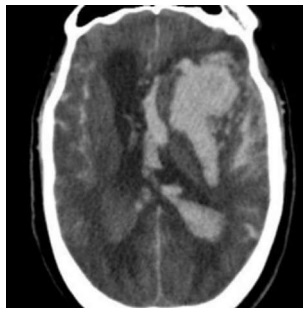

Uma mulher de 32 anos de idade, com antecedentes de ansiedade e enxaqueca, compareceu ao pronto-socorro

trazida por uma viatura do SAMU acompanhada por uma amiga, com relato de cefaleia holocraniana intensa, que teve início

duas horas antes, além de vômitos intensos, mal-estar e rebaixamento do nível de consciência durante o transporte. A seguir,

consta a tomografia computadorizada do crânio.